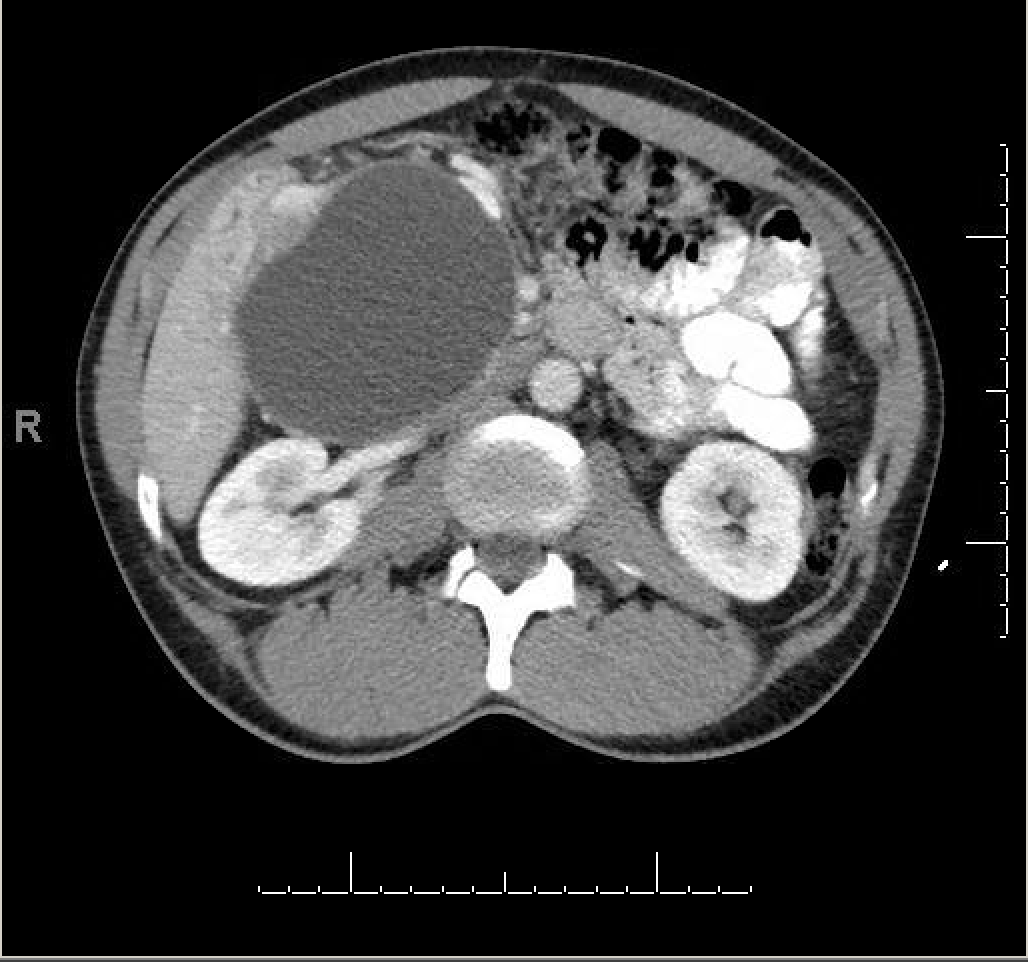

The providers were unsure. A CT scan of the abdomen was obtained to better define the mass. Here are some of the images:

The mass was thought to be either a large pancreatic pseudocyst, a low-grade cystic pancreatic neoplasm, or a duodenal duplication cyst.